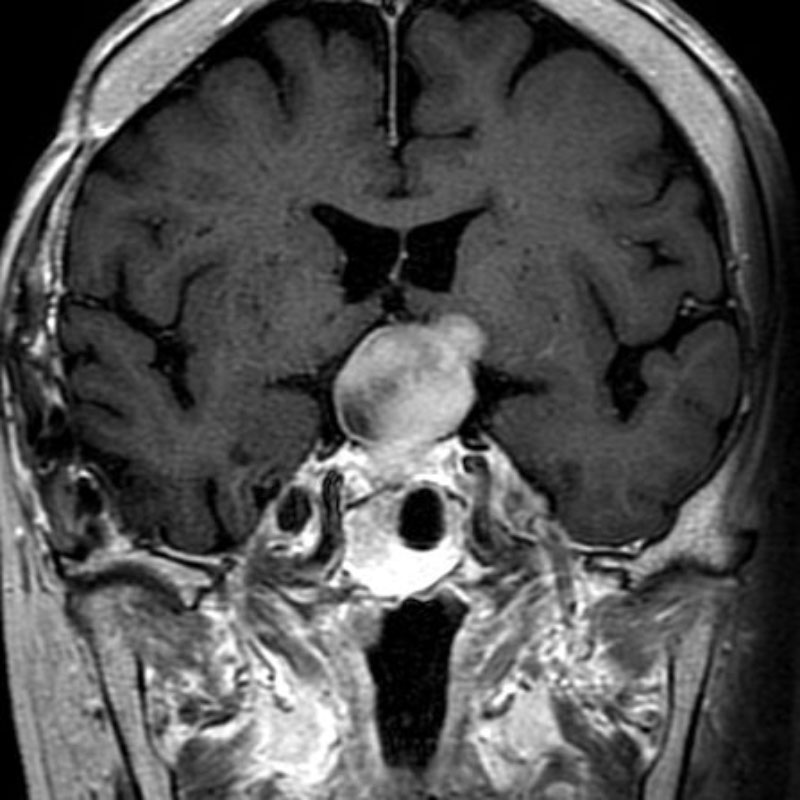

下垂体腺腫

頭蓋内腫瘍摘出術

No.’25_34 手術前1

No.’25_34 手術前2